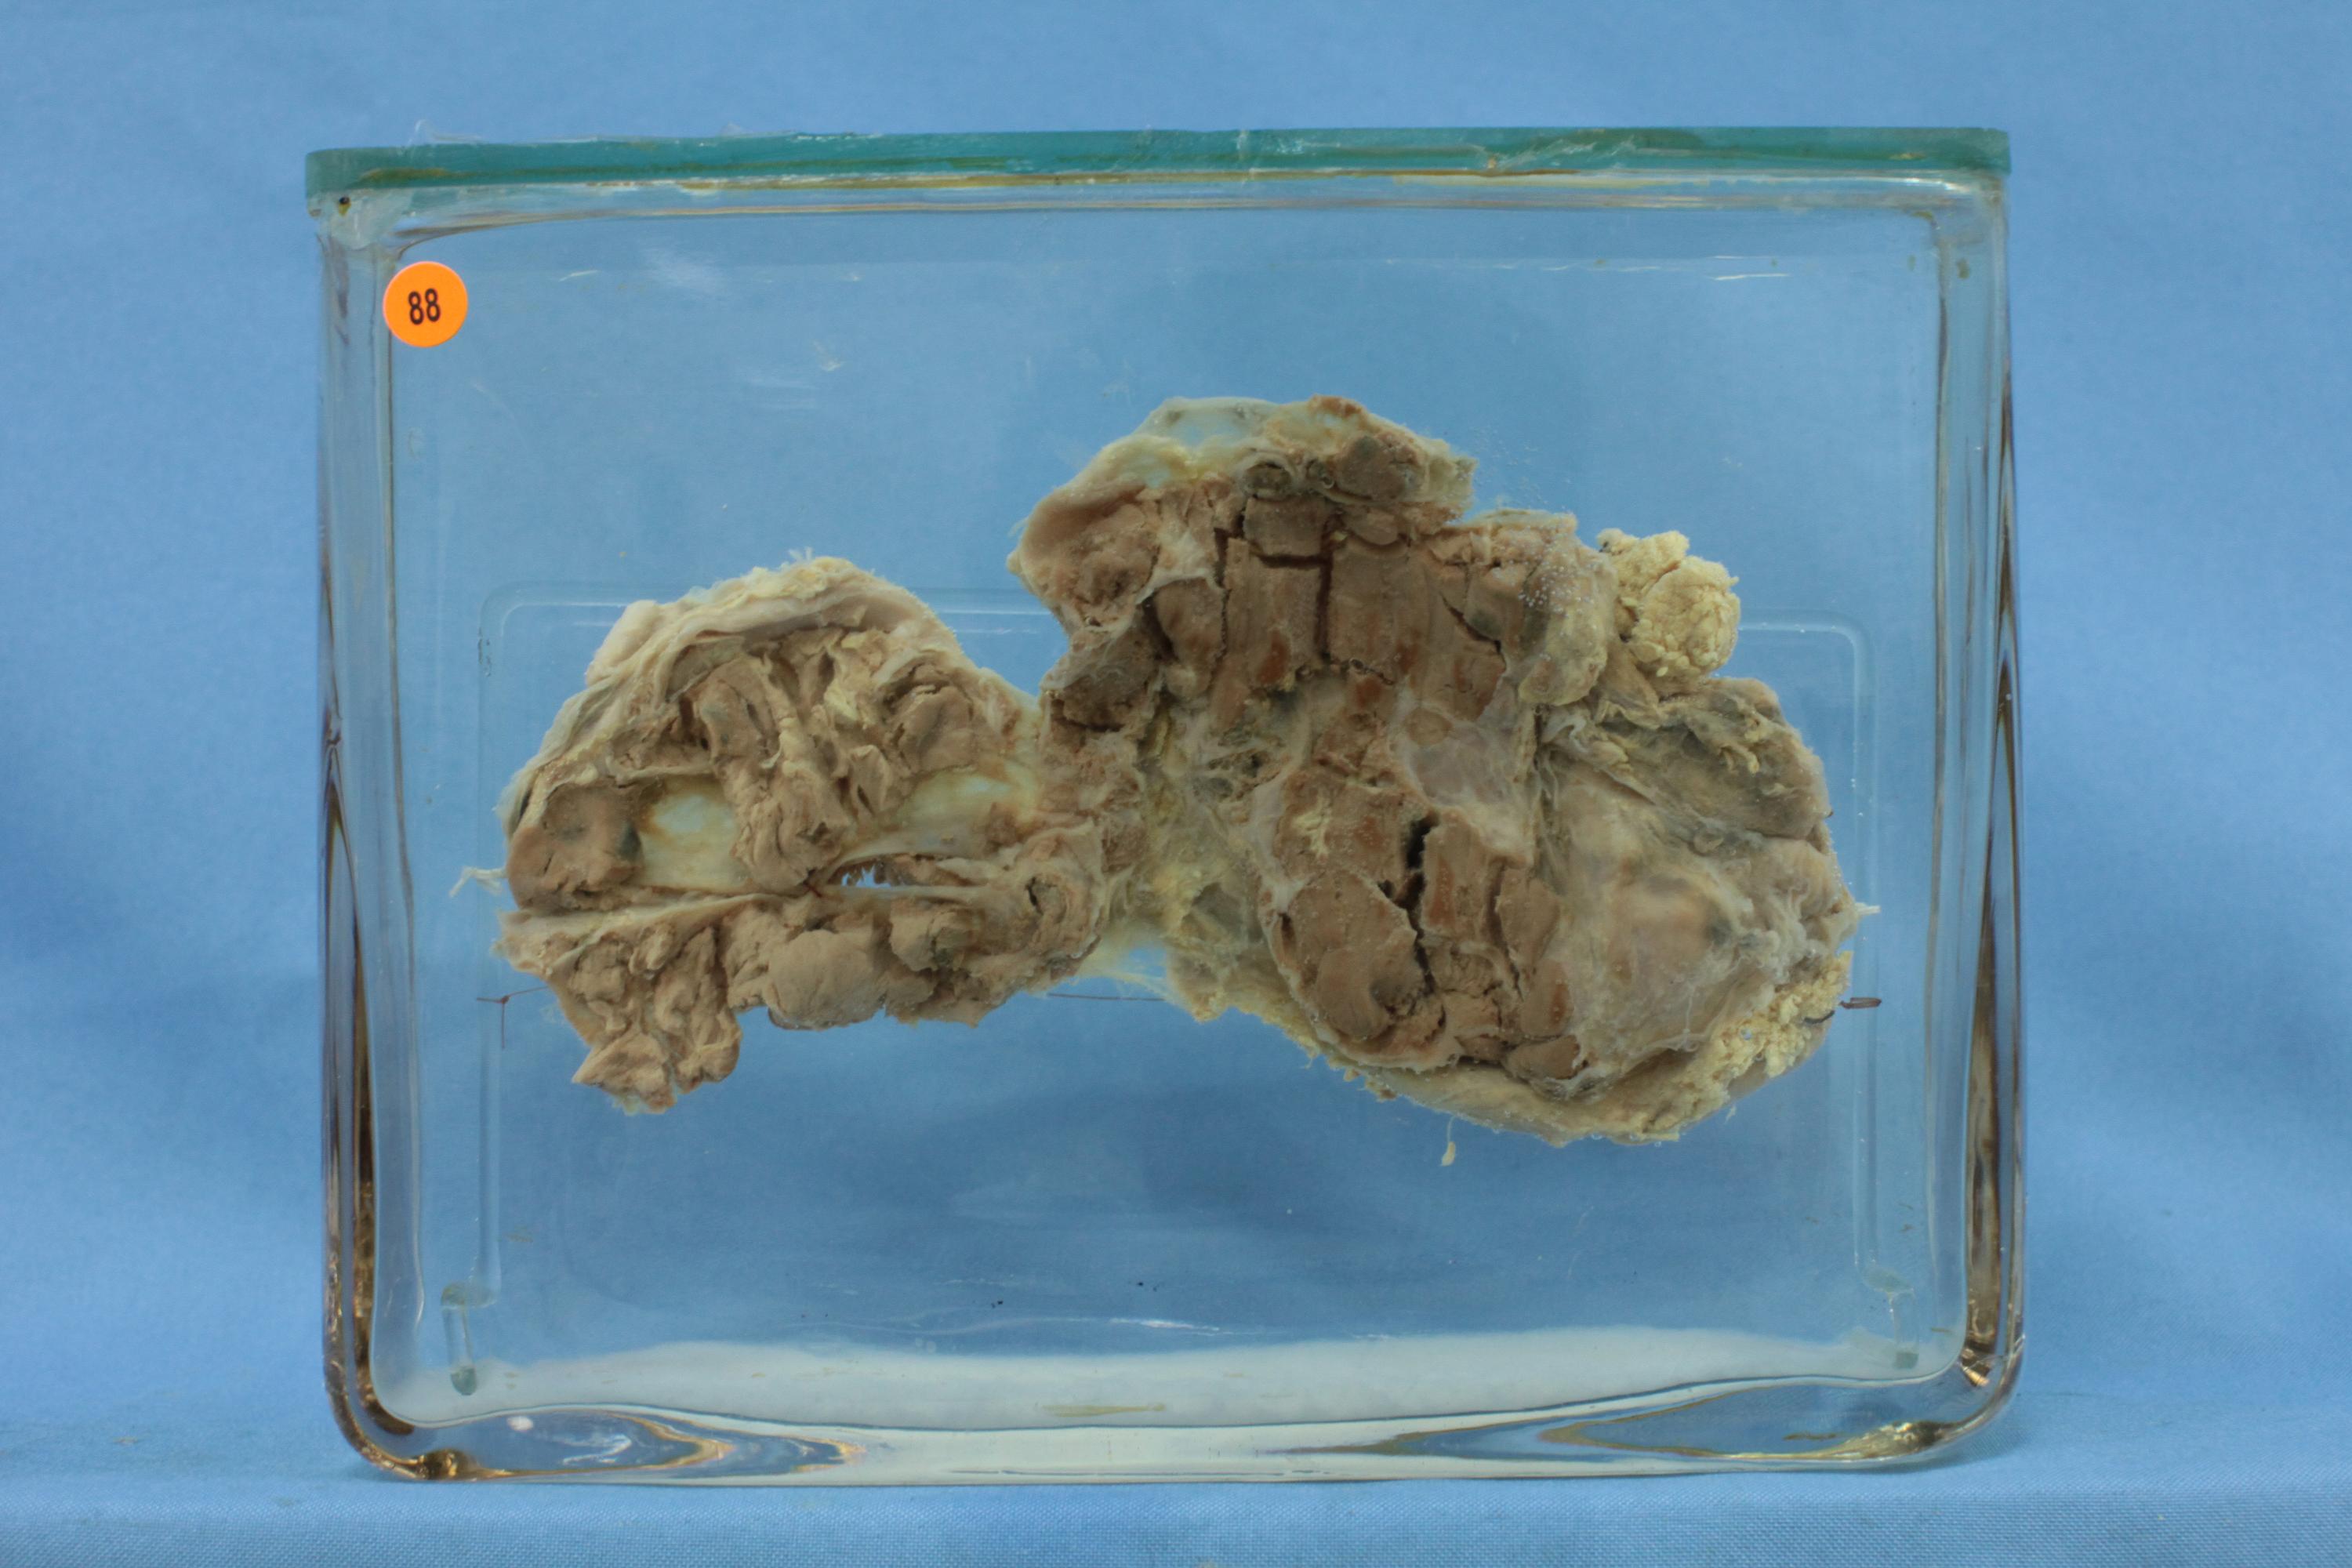

内分泌-73-88. 胸腺瘤(淋巴型)

患者男,36岁,切面见不规则形结节,呈灰白色,质实,伴少量出血坏死。